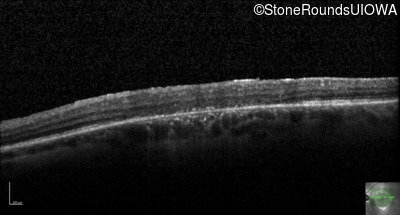

Optical Coherence Tomography - Left - 20/100 sc

Exemplar / OCT Stack